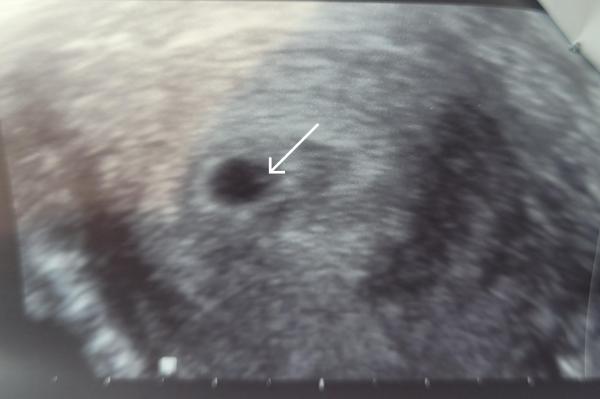

War gestern bei 5+0 bei der Bereitschaftsärztin weil ich so ein starkes Ziehen hatte und Angst hatte, dass es ne ELS sein könnte. Es hat sich was in der Gebärmutter eingenistet... und sie meinte man erkenne die embryonale Anlage, da als kleinen Punkt rechts... und für 5+0 sehe das normal aus. Ich habe es mit meinem Ultraschall von 5+2 verglichen, wo ich vor 3 Jahren ein Windei hatte und irgendwie seh ich gar keinen Unterschied. Kann der kleine Minipunkt echt Entwarnung geben? Wie sah das bei euch so früh aus?

Hier noch das Bild

Ja, dieser kleine Punkt ist tatsächlich der Unterschied zwischen Windei und keinem Windei. Ich drücke dir die Daumen, dass diesmal alles gut geht und du in zwei Wochen einen bisschen größeren Strich mit Herzschlag siehst

Bei nem Windei bleibt die Fruchthöhle leer. Das erste embryonale Anzeichen ist der Dottersack, der wird im Laufe der 6.ssw sichtbar. Also ja, alles zeitgemäss =)

Sieht nach einem winzigen Dottersack aus :) ich wünsche dir alles Gute! Ich habe auch letzten Monat ein Windei gehabt, in der 6 SSW war kein Punkt zu sehen so wie bei dir.